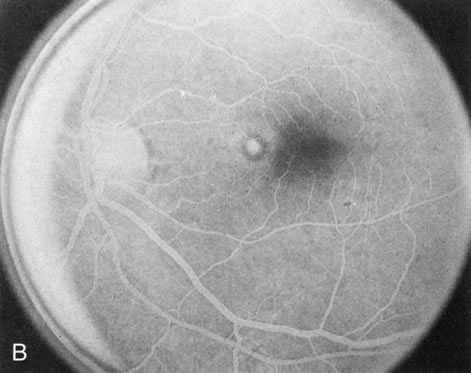

BEST'S VITELLIFORM MACULAR DYSTROPHY

The intact solid yellow egg yolk lesion in Best's vitelliform macular dystrophy (BVMD) typically shows hypofluorescence on FA due to blockage of the underlying choroidal fluorescence with the overlying retinal vasculature visible (Fig. 10A and, B). This finding places the lesion in front of the choroid, possibly within the RPE, but probably not within the neurosensory retina. There is no histopathology of the intact lesion to confirm this.

Fig. 10. Best's vitelliform macular dystrophy. The most characteristic angiographic finding in the solid yellow egg-yolk stage is blocked hypofluorescence (A, B). A morphologically mimicking lesion (pseudovitelliform degeneration) may be the result of leakage from the underlying choroid (C–E).

Histopathology in later stages of BVMD has shown an increase in lipofuscin in the RPE throughout the retina.23 If lipofuscin were within the intact egg-yolk lesion, this would block fluorescence. However, it is surprising that the “silent,” “dark” choroid seen in another disease with diffuse RPE lipofuscin accumulation (Stargardt's disease) does not occur in BVMD.

There are several acquired macular degenerations of different etiologies that have a macular lesion similar to the vitelliform stage of BVMD. FA may be helpful in identifying these cases of pseudovitelliform degeneration by showing leakage from the retinal capillaries or through the RPE and late staining of the lesions (Fig. 10CE). However, the electro-oculogram remains the most discriminating test because it is always abnormal in BVMD and usually normal in pseudovitelliform macular degeneration.